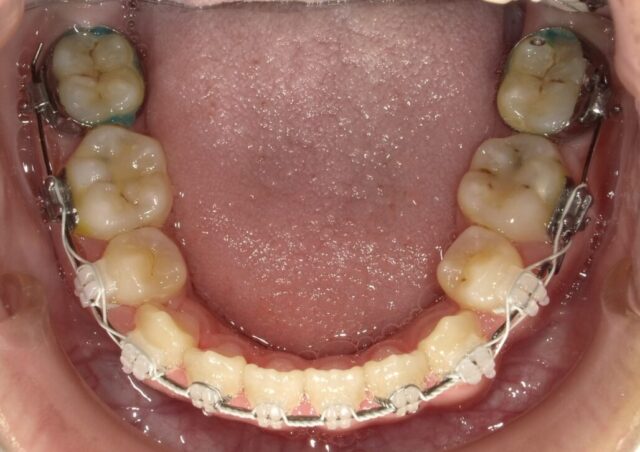

≪下顎咬合面観≫

2023年5月

2023年6月

2023年7月

2023年8月

2023年9月

2023年10月

2023年11月

2023年12月

2024年1月

2024年2月

2024年3月

2024年4月

2024年5月

2024年6月

2024年7月

2024年8月

2024年9月

2024年10月

2024年12月

2025年1月